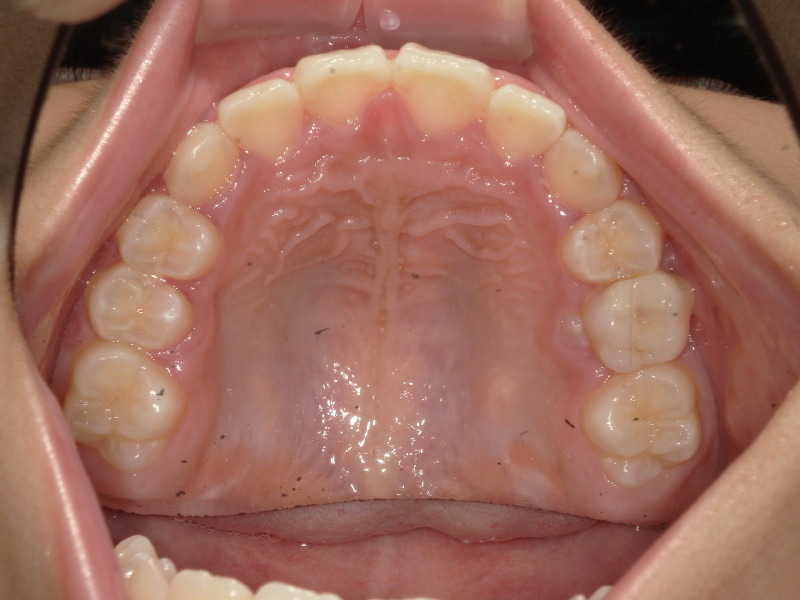

その後の歯並びの状態

装置をつけた後は歯が開いて見えますが、そこからマウスピースや舌の使い方、普段の鼻呼吸を続けることで正しく顎骨が成長していきます。

装置を外してからも順調にアクティビティーをすすめ、全ての項目が終了、マウスピースの身で続けてくれていたのですが、3番目の歯が入る頃にはここまで綺麗になっています。

しっかりと歯が綺麗なアーチに並んでいます。